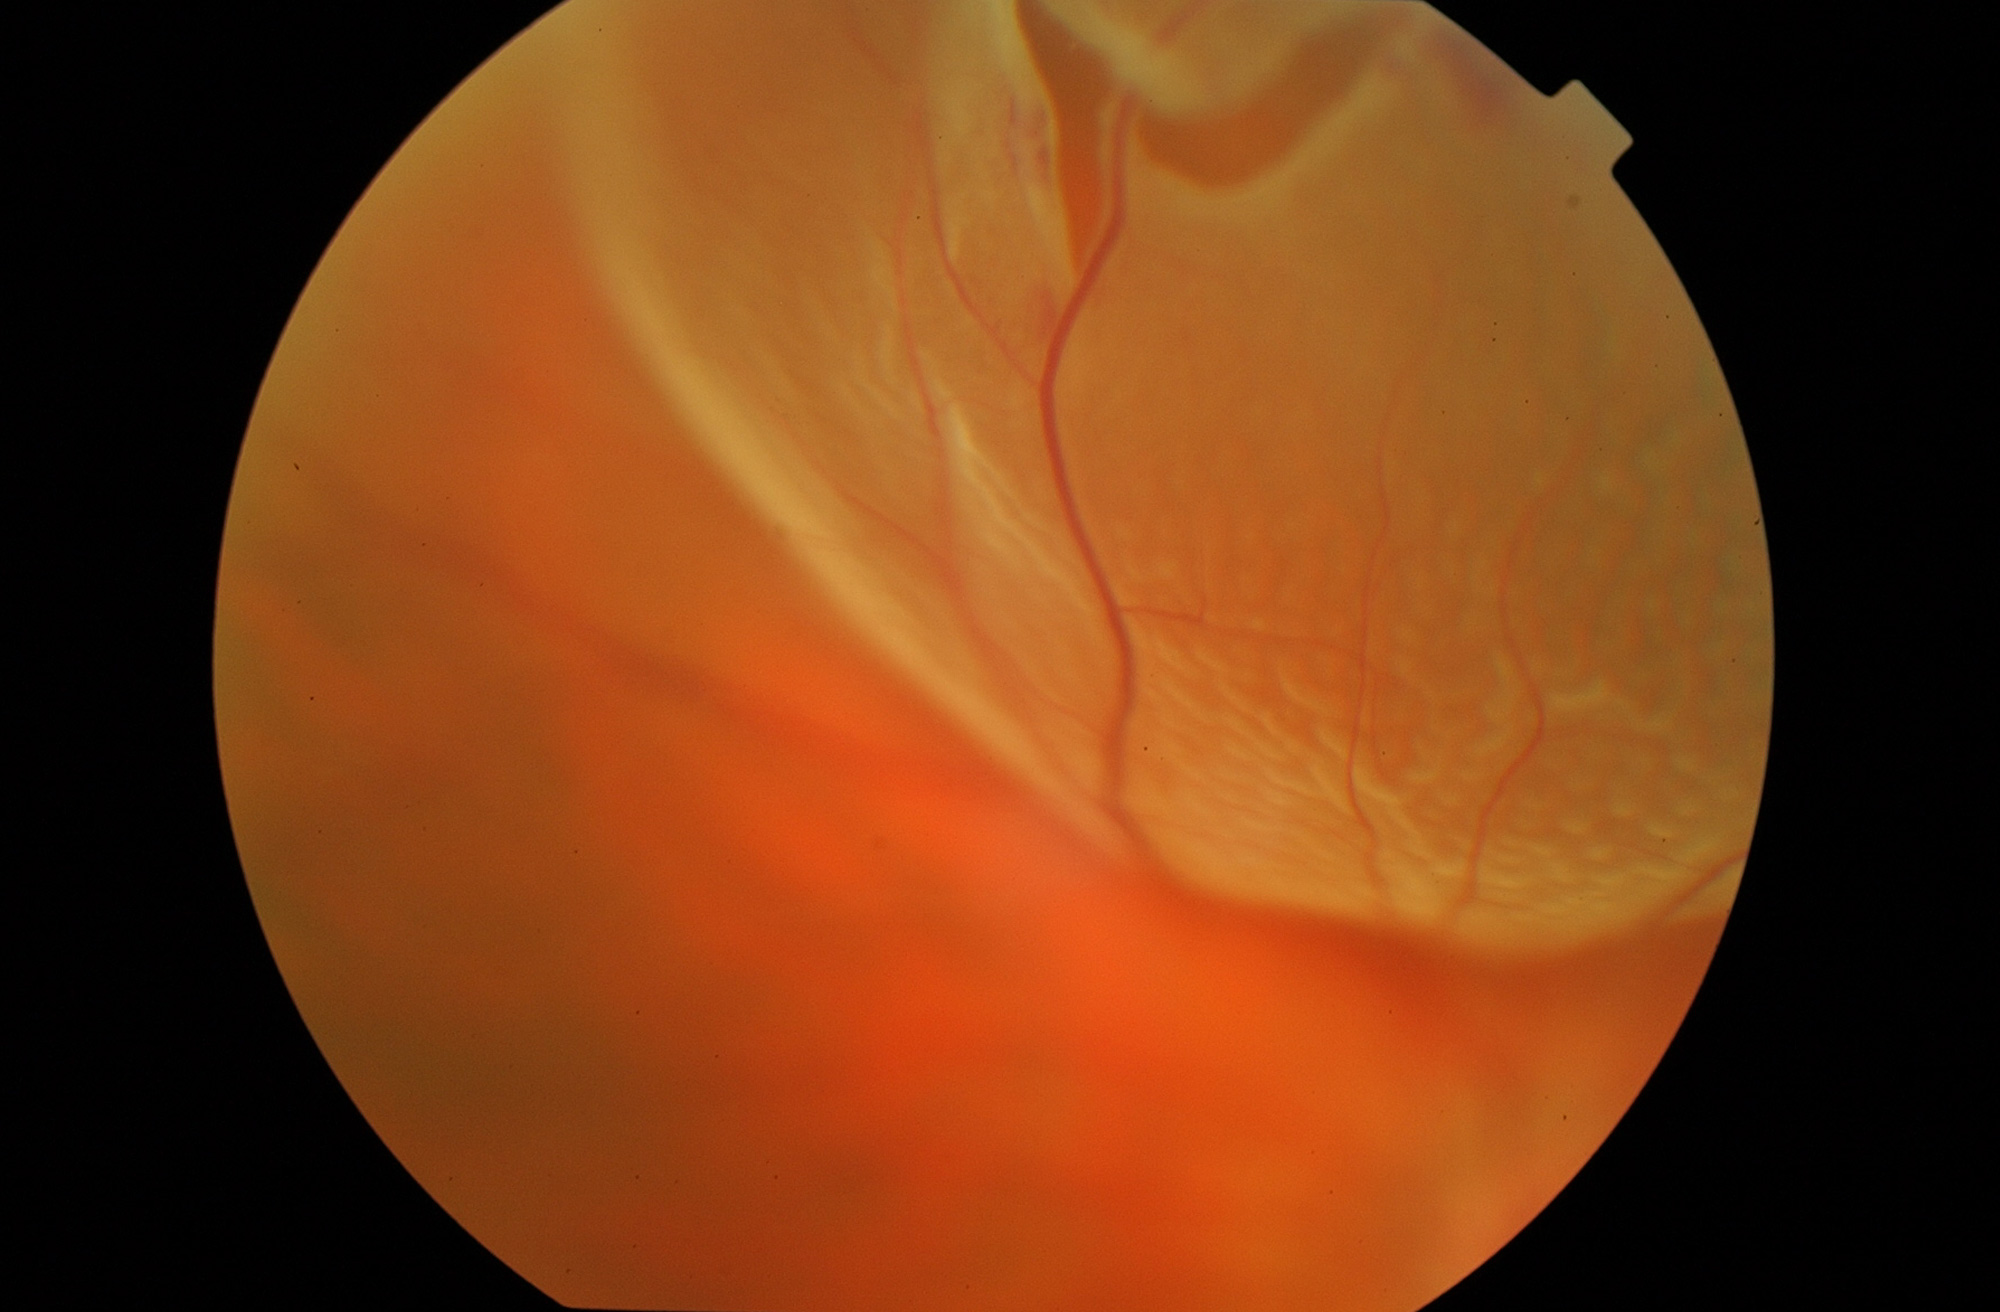

El objetivo de la vitrectomía es la reparación anatómica y funcional de la retina para devolver la máxima visión posible.

El objetivo de la cirugía del desprendimiento de retina es recolocar la retina en su lugar para recuperar la máxima visión posible.